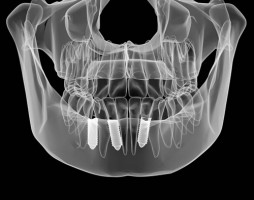

A thorough examination and x-rays give a lot of information on the amount of bone you have. In addition it may be recommended that you have a CT scan taken to provide more detail.

A CT (computerised tomography) scan gives the implant dentist a 3D image of the bone volume and shape of your jaws. The dentist can then assess whether the patient is suitable for tooth implant treatment. The scan may also be used to create a surgical guide to accurately place your implant.

Computer-aided dental implant surgery enables the dentist to place the implants more accurately, especially in complex cases. The technology allows the dentist to plan the surgery using a CT scan, specialist software and a surgical guide to accurately position your implants, making the process very precise.